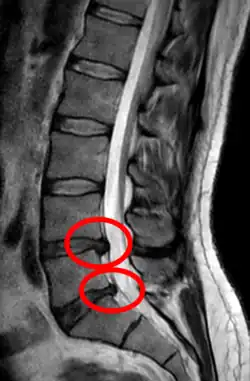

- Magnetic resonance imaging is the gold standard study for confirming a suspected LDH. With a diagnostic accuracy of 97%, it is the most sensitive study to visualize a herniated disc due to its significant ability in soft tissue visualization. MRI also has higher inter-observer reliability than other imaging modalities. It suggests disc herniation when it shows an increased T2-weighted signal at the posterior 10% of the disc. Degenerative disc diseases have shown a correlation with Modic type 1 changes. When evaluating for postoperative lumbar radiculopathies, the recommendation is that the MRI is performed with contrast unless otherwise contraindicated. MRI is more effective than CT in distinguishing inflammatory, malignant, or inflammatory etiologies of LDH. It is indicated relatively early in the course of evaluation (<8 weeks) when the patient presents with relative indications like significant pain, neurological motor deficits, and cauda equina syndrome. Diffusion tensor imaging is a type of MRI sequence used for detecting microstructural changes in the nerve root. It may be beneficial in understanding the changes that occur after herniated lumbar disc compresses a nerve root, and might help in differentiating the patients that need surgical intervention. In patients with a high suspicion of radiculopathy due to lumbar disc herniation, yet the MRI is equivocal or negative, nerve conduction studies are indicated.[46] T2-weighted images allow for clear visualization of protruded disc material in the spinal canal.

A rather severe herniation of the L4–L5 disc

Example of a herniated disc at L5–S1 in the lumbar spine